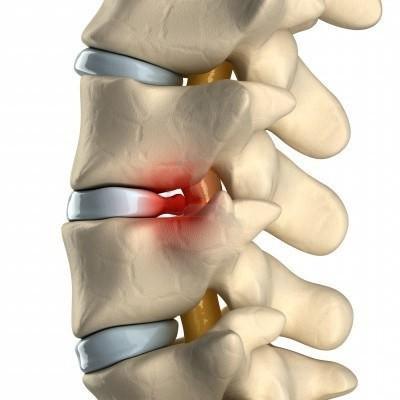

- Остеохондроз – процесс разрушения межпозвоночного диска, при котором позвонки сближаются, защемляя нервы. Обостряется сезонно, после гиподинамии, нагрузок. Боли длительные, средней интенсивности, разлитые. Схожая симптоматика, обычно, наблюдается и в суставах других групп;

- Грыжа, протрузия межпозвоночного диска – выход диска или его содержимого за пределы позвоночного столба, в спинномозговой канал. Происходит сдавливание большого количества нервной ткани, потому кроме очень интенсивных болей наблюдаются онемения ног, гипертонус, спазм мышц в них, их слабость;

Межпозвоночная грыжа

При грыже боли проявляются в момент нагрузки на поясницу. Они имеют острый «простреливающий» характер, и только спустя время болевой синдром «спускается» в низ живота.

Поясничные грыжи обычно находятся между третьим, четвертым и пятым поясничными позвонками и между пятым позвонком и крестцом. Зачастую грыжей защемляются нервы, ведущие в нижние конечности. Боль при межпозвонковых грыжах острая. Больному тяжело нагибаться, вставать, порой даже лежать на ровной поверхности.